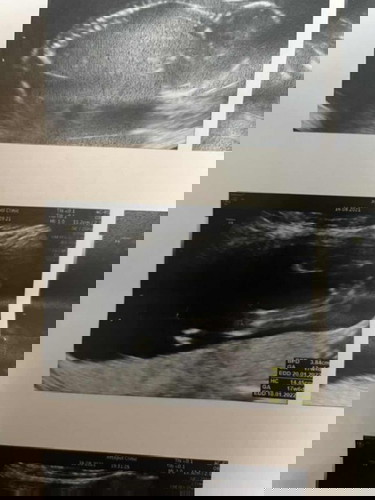

แม่ๆว่าได้เพศอะไรคะ ญ/ช

หมอไม่ได้แจ้งอะไร มันใช่ระหว่างขาเด็กไหมคะ ท้องแรกค่ะ 17w3d🥰

ใช่ค่ะแต่ไม่แน่ใจ น่าจะญ.นะคะ

ผู้หญิงค่ะ

น่าจะผ.ญค่ะ

ญค่ะ